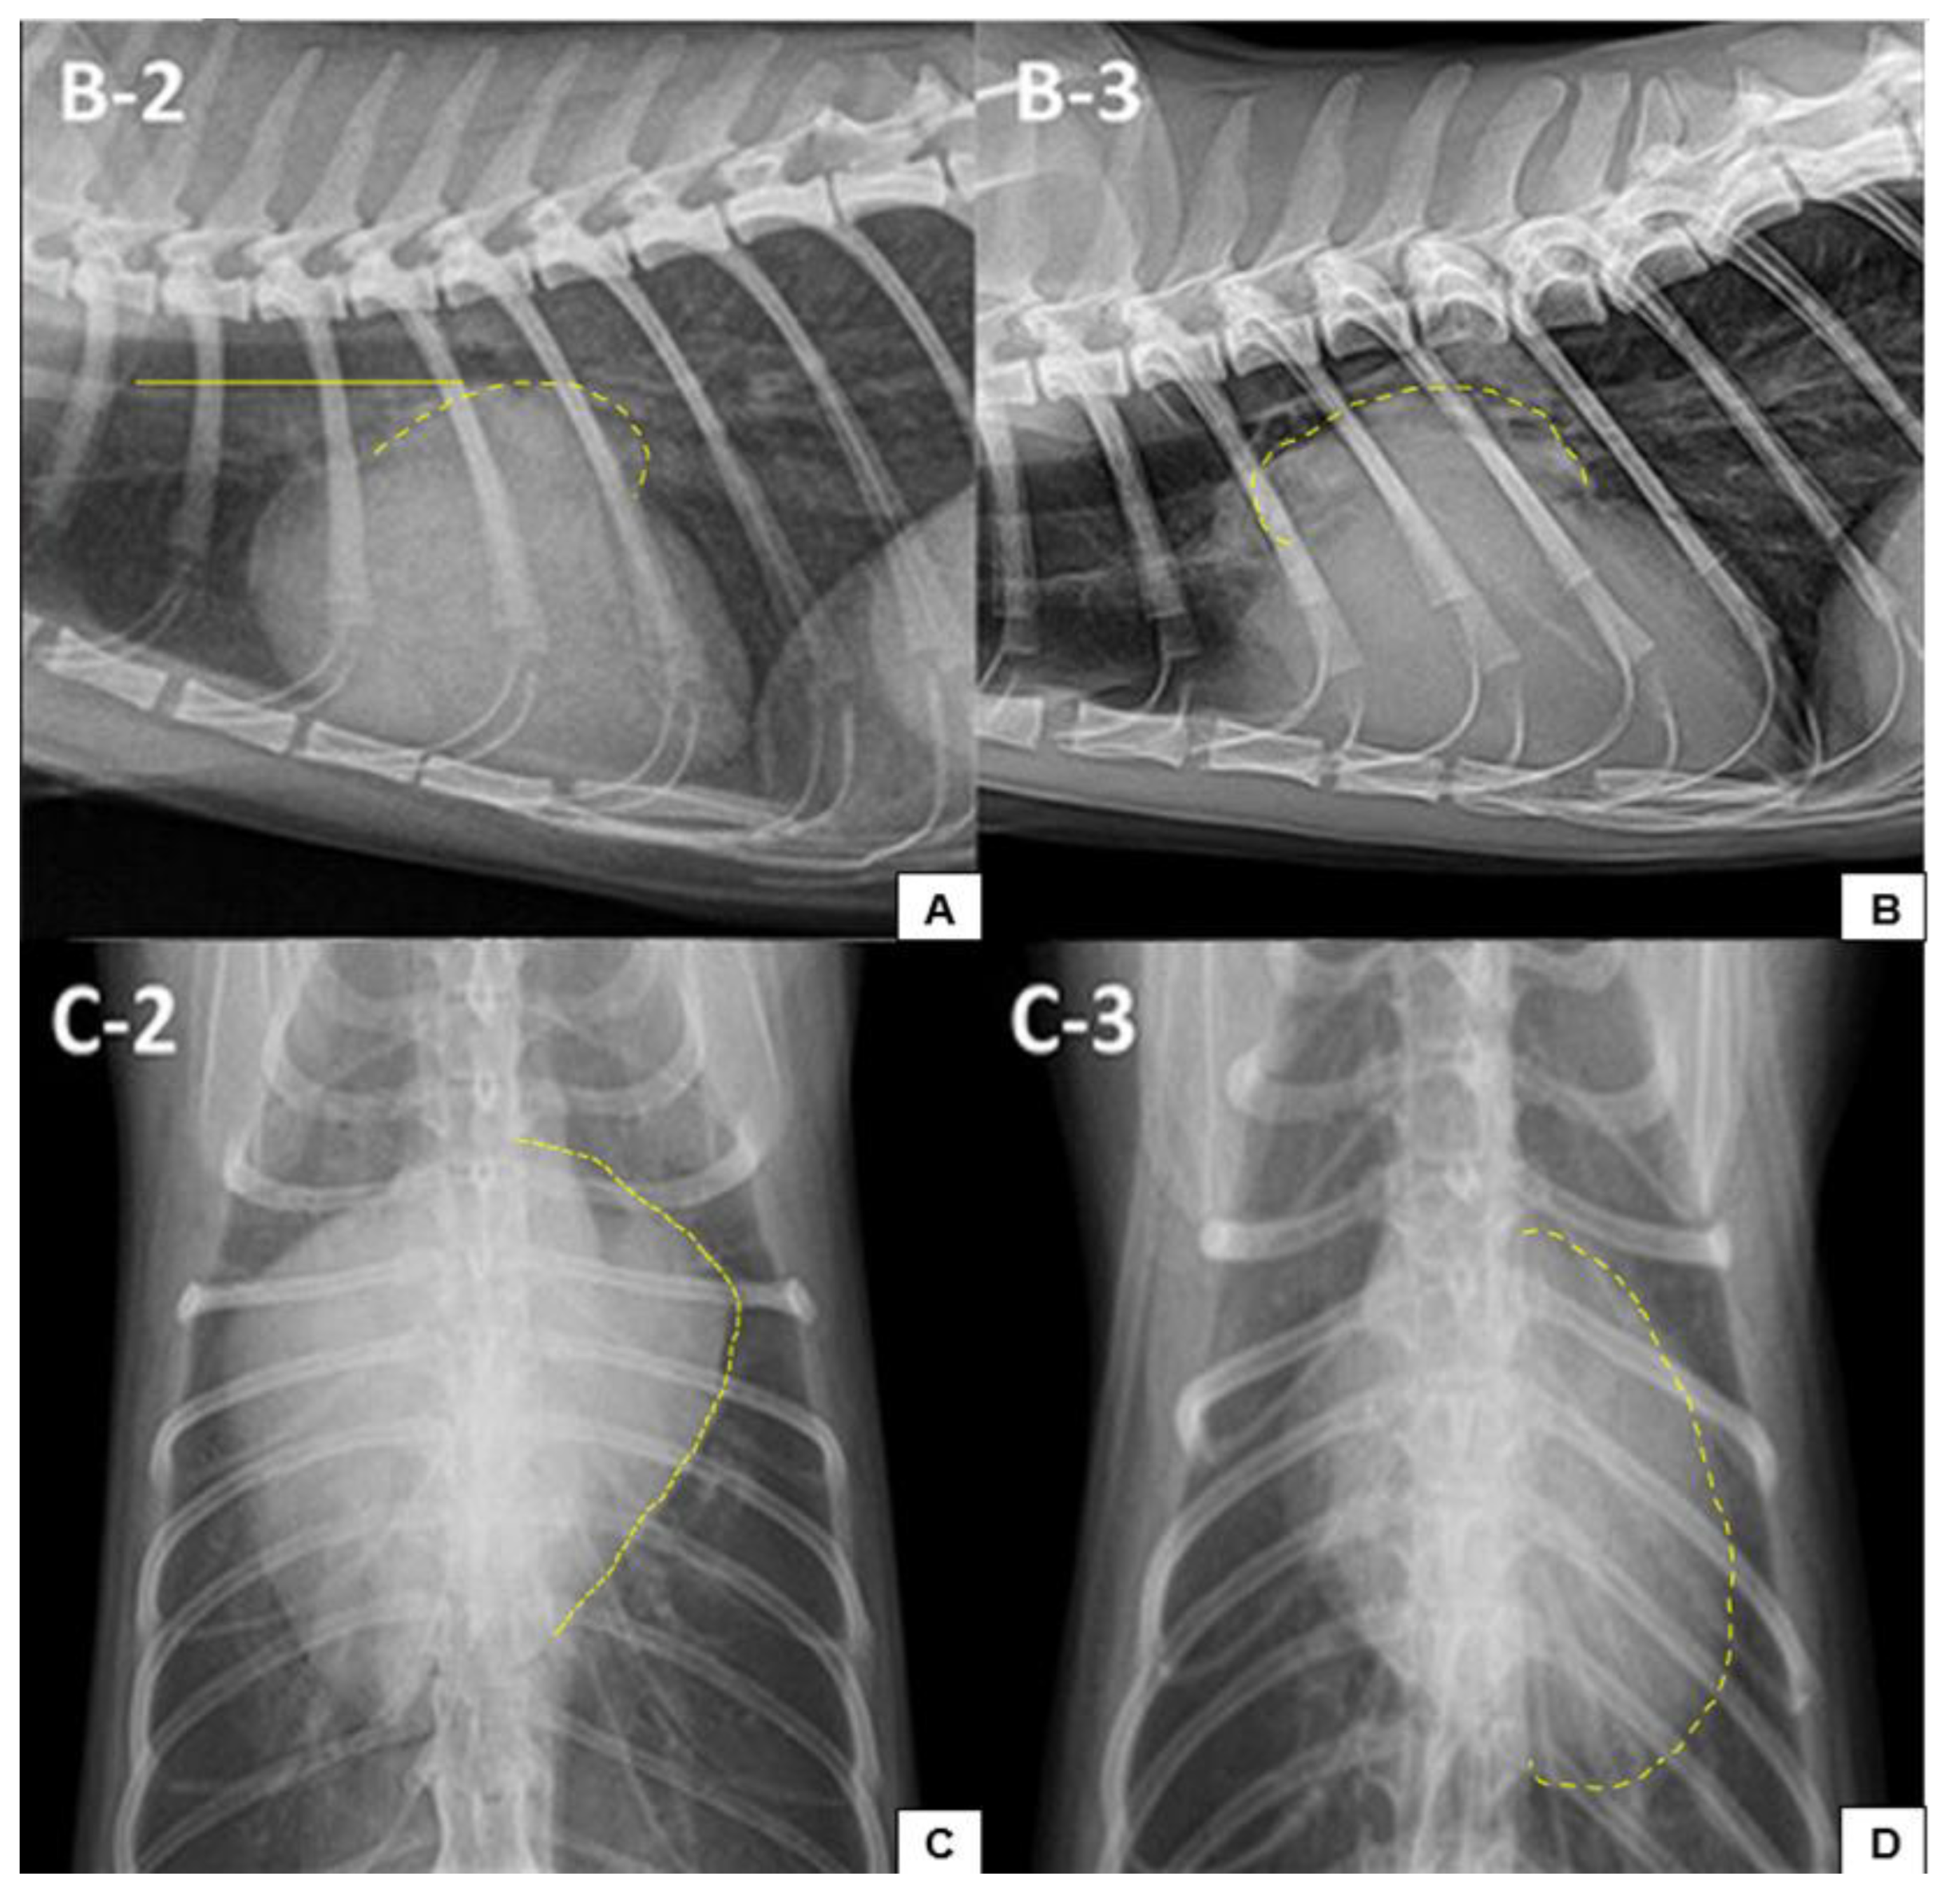

- Guglielmini, C.; Diana, A. Thoracic radiography in the cat: Identification of cardiomegaly and congestive heart failure. J. Vet. Cardiol. 2015, 17, S87–S101. [Google Scholar] [CrossRef]

- Kim, S.; Lee, D.; Park, S.; Suh, G.H.; Choi, J. Radiographic findings of cardiopulmonary structures can predict hypertrophic cardiomyopathy and congestive heart failure in cats. Am. J. Vet. Res. 2023, 84, ajvr.23–01.0017. [Google Scholar] [CrossRef]

- Litster, A.L.; Buchanan, W. Vertebral scale system to measure heart size in radiographs of cats. Am. Vet. Med. Assoc. 2000, 216, 210–214. [Google Scholar] [CrossRef]